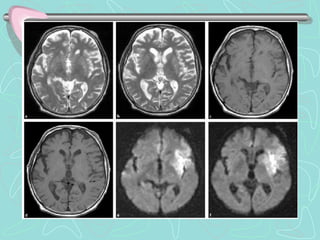

PENUMBRA ISQUEMICA

Core and penumbra in acute stroke imaging.

The infarct core, presumptively identified by an abnormality in a DWI image, represents tissue that

cannot be salvaged.

The ischemic penumbra represents tissue that is threatened by ischemia, but may still be saved by

timely therapy. The penumbra is presumptively identified as that tissue that is normal in early DWI

images, but abnormal in maps of CBF.

(a) Early DWI image shows several small closely clustered acute infarcts in the left corona radiata. An MTT map

(b) shows a much larger region of impaired perfusion, theoretically representing tissue at risk. However, a follow-up

T2-weighted FLAIR image

(c) shows that the infarct has not grown substantially.

Preservation of penumbral tissue, as demonstrated by this case,

… is the goal of acute stroke therapy.